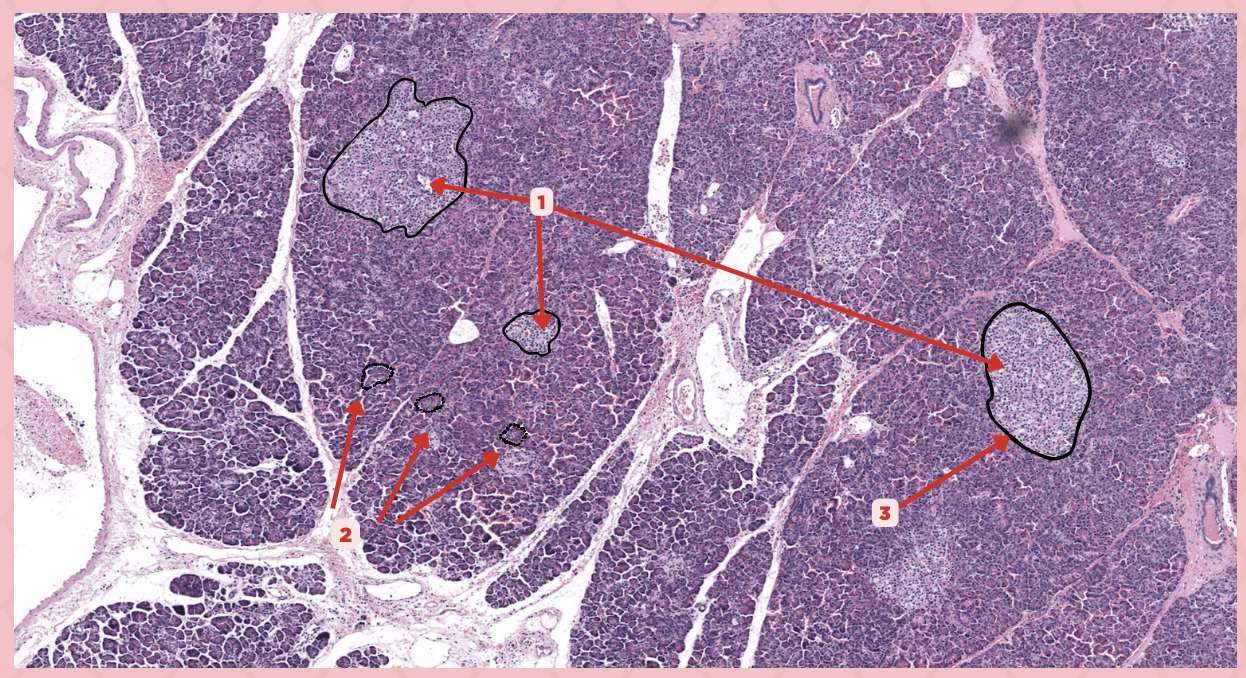

Parathyroid

Identify the specimen.

Chief Cells

Identify the specimen labeled as 1.

Oxyphil Cells

Identify the specimen labeled as 2.

Adipocytes

Identify the specimen labeled as 3.

Capillaries

Identify the specimen labeled as 4.

Newborns

Pointer #2 is hardly present in the parathyroid glands of _____.

Parathyroid

Identify the specimen.